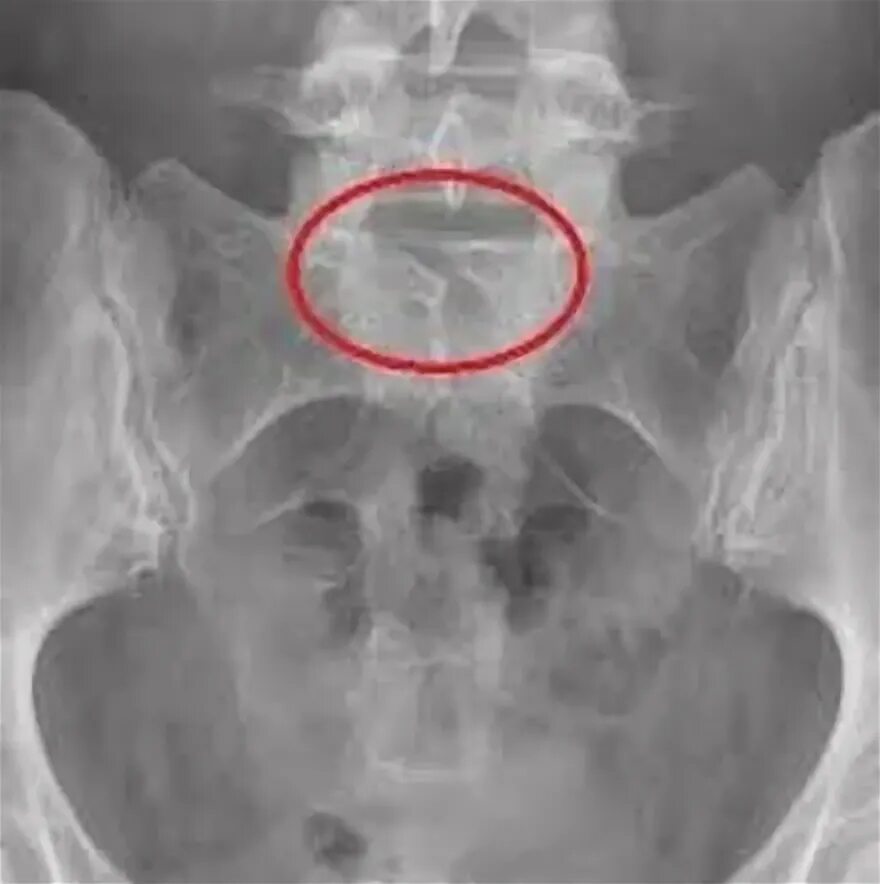

Незаращение дужки позвонка